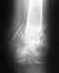

Re: перипротезный перелом